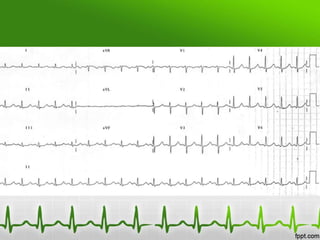

ECG 1

ECG 2

After Potassium Correction

Potassium of 9.4 mmol/L